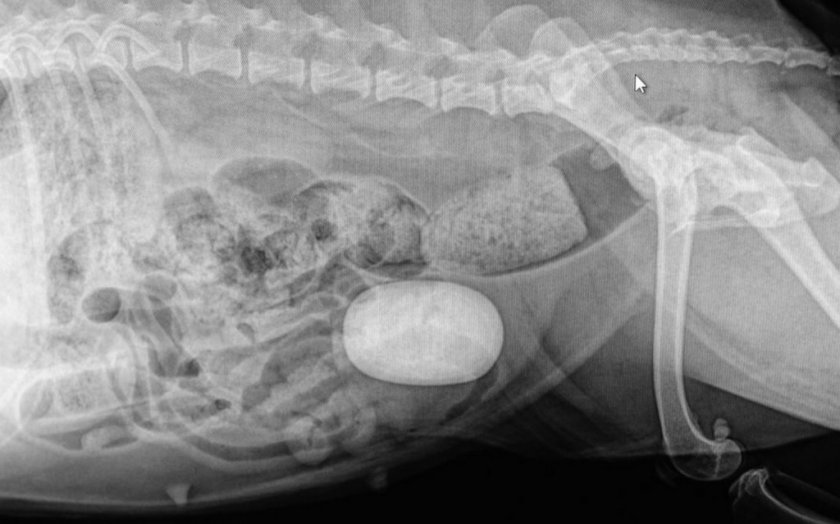

Как проходит диагностика

Большинство камней видны на рентгенограммах или при ультразвуковом исследовании мочевого пузыря. Но некоторые из них не видны, поскольку их минеральный состав не отражает рентгеновские лучи. Для их обнаружения потребуется ультразвуковое обследование.

| Струвиты | Видны на рентгене. Диагностируется повышенный уровень pH мочи, повышенный уровень фосфора или аммиака в ней. |